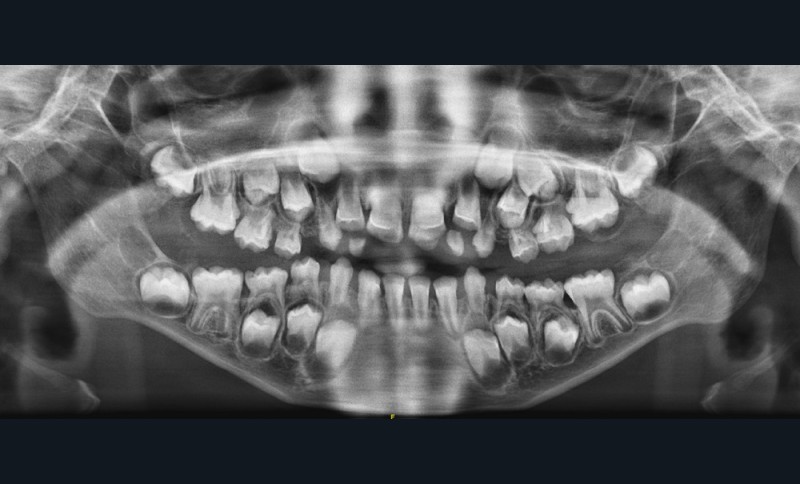

En 2022, la patiente ne présentait en bouche que 6 dents à la mandibule : 31, 32, 73, 41, 42 et 83. Hormis 63, aucune dent temporaire maxillaire n’a fait son éruption cependant à l’examen panoramique, la formule dentaire est complète (fig. 1).

En 2023, d’un point de vue dentaire, Julia présente une absence et un retard d’éruption dentaire avec la présence partielle en bouche de 10 dents (fig. 2 et 3). Selon la mère de la patiente, la perte des incisives temporaires mandibulaires aurait eu lieu entre l’âge de 4 et 5 ans.

En revanche, elle ne se rappelle pas avoir déjà vu sa fille avec des dents au maxillaire. Par ailleurs, le contrôle de plaque est bon et aucune lésion carieuse n’est détectée.